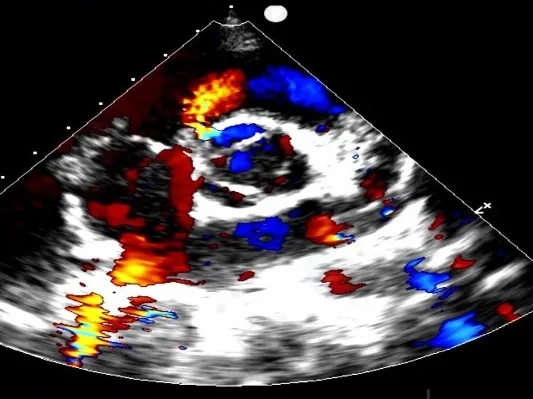

门诊心脏彩超提示:

超声多切面示:室间隔膜周部可见连续中断,局部不规则向右室膨出,呈“囊袋状”,断端回声增强,测缺口大小:左室面6.5mm、右室面2.5mm,隔瓣下残缘5mm,彩色血流示:室水平左向右分流,Vmax 473cm/s,Pgmax 89 mmHg。

各房室腔大小及大血管内径未见异常。各瓣膜厚度、弹性、开放幅度正常,彩色血流示:三尖瓣反流(少量),长度1.51cm、面积1.4cm2,容积1.0ml,Vmax 216cm/s,PGmax 16mmHg。据三尖瓣反流法估测肺动脉收缩压为28 mmHg;左室收缩功能正常,EF为74%。

术前超声与DSA复测

VSD(膜周部):室间隔膜部瘤,左室面6.5mm,右室面呈“瘤样”结构,瘤体深度7mm,出口2mm。

该病灶呈现为“长隧道、大瘤底、小出口”的细腰形态,且位置紧邻主动脉瓣与三尖瓣,解剖结构较为复杂。此形态特征使得可降解封堵器在植入过程中的定位与释放面临较大挑战。